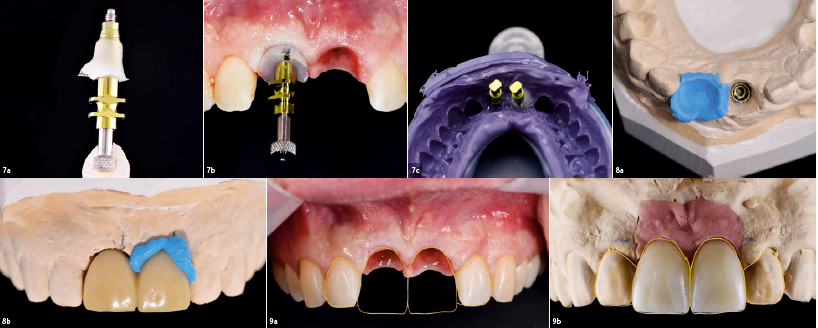

Το εκμαγείο γύψου που προέκυψε διαμορφώθηκε στην περιοχή του 21. Στη συνέχεια, χρησιμοποιήθηκε ένα αποτύπωμα σιλικόνης για να καταγραφεί το προφίλ ανάδυσης του γεφυρώματος στον 21 της προσωρινής γέφυρας (εικ. 7A-c). Αυτή η πληροφορία μεταφέρθηκε σε ένα κλασικό άξονα αποτύπωσης, με συνέπεια ένα εξατομικευμένο αποτύπωμα στην περιοχή του 21 (εικ. 8a&b). Στο επόμενο στάδιο, εκτιμήθηκε η κατάσταση με ψηφιακή ανάλυση σχεδιασμού χαμόγελου (εικ. 9a&b). Η αξιολόγηση αποκάλυψε μία δυσανάλογη κατανομή του όγκου μεταξύ των κεντρικών και πλαγίων τομέων. Οι πλάγιοι τομείς ήταν πολύ στενοί σε σχέση με το ευρύ και τετράγωνο σχήμα των κεντρικών τομέων. Για να βελτιωθεί η αρμονία, ο όγκος θα πρέπει να κατανέμεται μεταξύ των τεσσάρων τομέων. Κατασκευάστηκαν νέες κοχλιούμενες προσωρινές αποκαταστάσεις. Πριν από αυτό, ένα κέρινο πρότυπο προσαρμόστηκε και δοκιμάστηκε ενδοστοματικά για να οπτικοποιηθεί το τελικό αποτέλεσμα. Δημιουργήθηκε ένα κλειδί σιλικόνης για να κτιστούν πρώτα οι πλάγιοι τομείς με ένα προσωρινό πολυμερές υλικό.

Εικ. 7A-c

Αποτυπώματα των εμφυτευμάτων στην περιοχή των 11 και 21 με εξατομικευμένο και κλασικό άξονα αποτύπωσης και το εκμαγείο που κατασκευάστηκε με βάση αυτά τα αποτυπώματα.

Εικ. 8a&b

Εκμαγείο εμφυτευμάτων. Η βασική περιοχή στην θέση του 21 τροποποιήθηκε και το προφίλ

Eικ. 9a&9b

Aνάλυση και σχεδιασμός με την χρήση της μεθόδου ψηφιακής σχεδίασης χαμόγελου